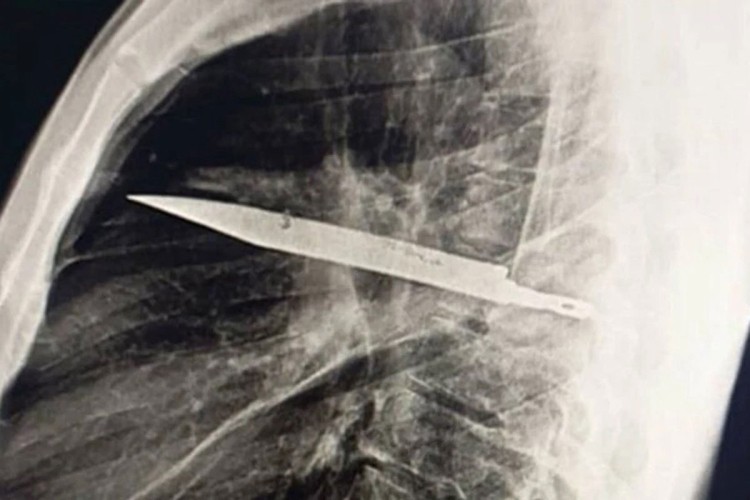

Nakon što je urađen rendgen, otkriven je "oštar metalni predmet", a ljekari su shvatili da je u pitanju nož, okružen "gnojem i nekrotičnim tkivom". Nož je u tijelo ušao kroz desno rame.

Hitno je preporučena operacija, tokom koje su ljekari uspjeli da izvade nož, a muškarac je proglašen dovoljno stabilnim da se već 10 dana kasnije vrati kući.

U izvještaju je ipak naglašeno koliko je imao sreće, jer je "iako se pacijent dobro oporavio nakon operacije, postojala značajna opasnost da zadržani nož dovede do smrtnog ishoda".

Stručnjaci su objasnili da je razlog zašto je pacijent uspio da preživi toliko dugo sa nožem u grudima taj što je njegovo tijelo uspjelo da "obmota strano tijelo fibroznom kapsulom (čvrstim zaštitnim slojem tkiva), čime je ograničilo upalu i oštećenje tkiva".